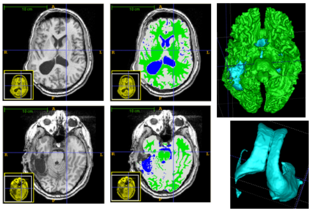

Experiments: Multi-modal registration and tissue segmentation

We conducted experiments with the application of the ABC tool to multi-modal image data of 5 TBI cases provided by DBP partner UCLA. The tool includes co-registration of multiple modalities via mutual-information linear registration, and a nonlinear registration (high-deformable fluid registration) of a probabilistic normative atlas for segmentation of healthy tissue. The following results show feasibility of multi-modal registration and segmentation of normal tissue. Pathology is segmented via postprocessing using 3D user-supervised level-set evolution.

Case 1: Segmentation of 5channel TBI data with ABC. Lesions and ventricles segmented with additional 3D level-set segmentation.

Case 2: Segmentation of 5channel TBI data with ABC. Lesions and ventricles segmented with additional 3D level-set segmentation.

Case 3: Segmentation of 5channel TBI data with ABC. Lesions and ventricles segmented with additional 3D level-set segmentation.